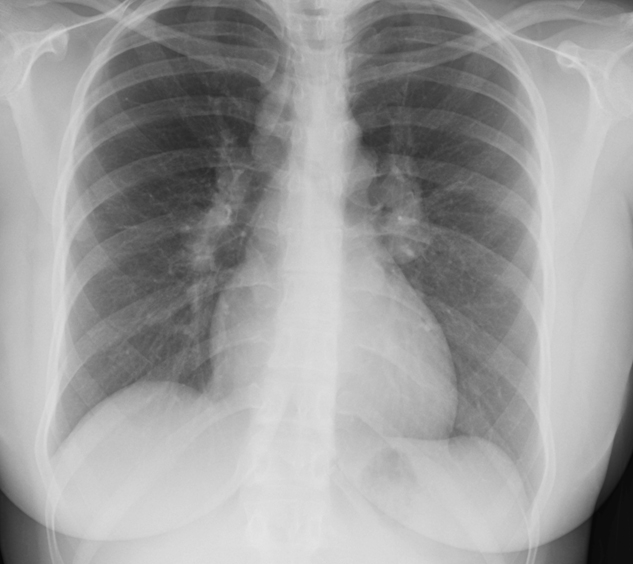

72yo with 4month hx leg swelling & increased abdominal girth. 2-year hx progressive sob. was a sandblaster.

silicosis

give o2